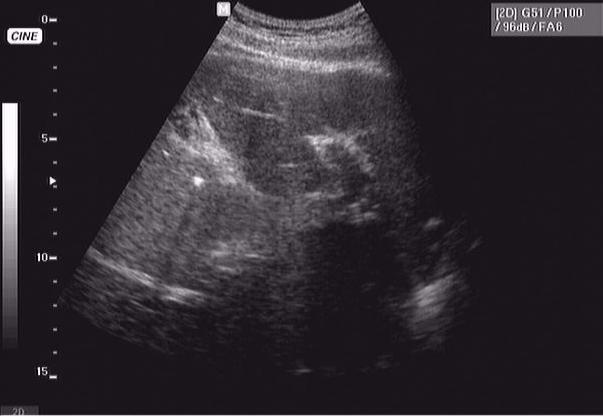

76 летний пациент - конкремент желчного протока, печень правая - 178 мм, левая - 62 мм

сахарного диабета нет, зато есть уртикарная сыпь... шистосомоз?

Онищук76 33.JPG

Онищук76 44.JPG

Онищук76 11.JPG